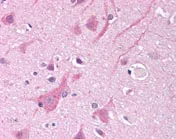

Immunohistochemistry (Formalin/PFA-fixed paraffin-embedded sections) - Anti-Nav1.5/SCN5A antibody (AB116706)

ab116706, at 5-10 μg/ml, staining Nav1.5/SCN5A in Formalin-fixed, Paraffin-embedded Human Brain cortex tissue by Immunohistochemistry followed by biotinylated secondary antibody, alkaline phosphatase-streptavidin and chromogen.